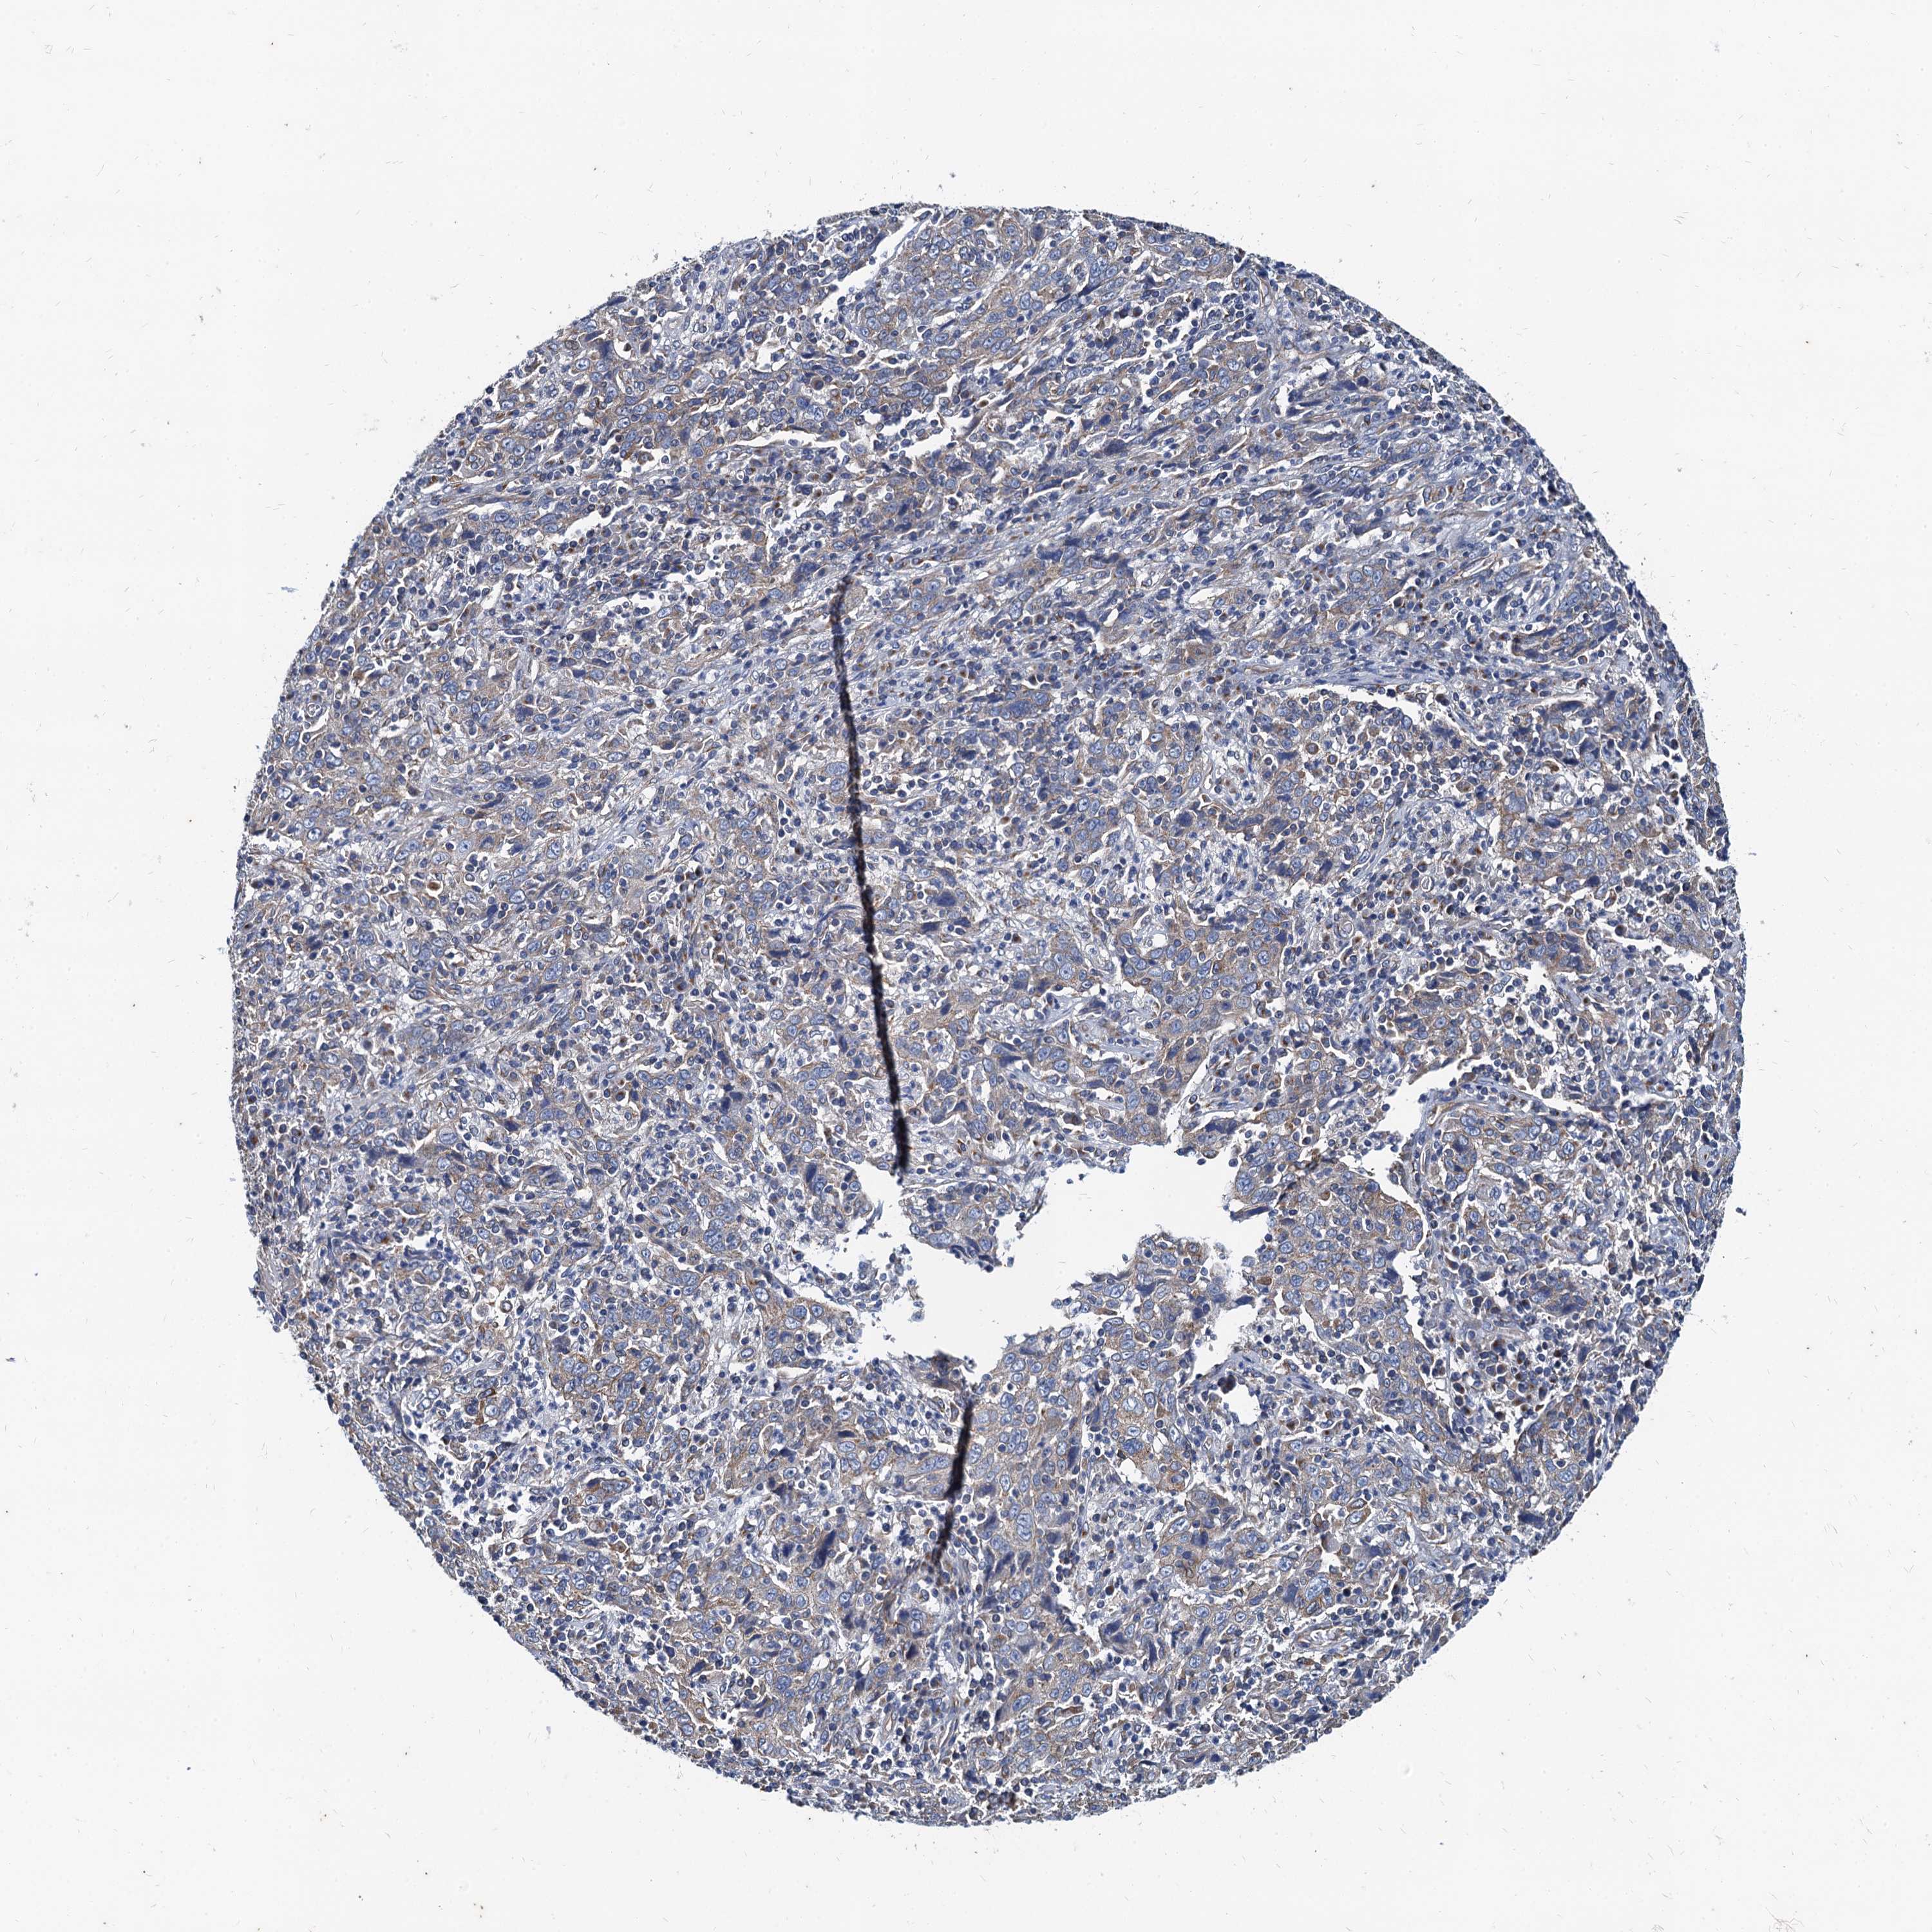

CERVICAL CANCER - Protein expressioni

A mouse-over function shows sample information and annotation data. Click on an image to view it in a full screen mode. Samples can be filtered based on level of antibody staining by selecting one or several of the following categories: high, medium, low and not detected. The assay and annotation is described here.

Note that samples used for immunohistochemistry by the Human Protein Atlas do not correspond to samples in the TCGA dataset.

Antibody stainingi

Antibody staining in the annotated cell types in the current human tissue is reported as not detected, low, medium, or high, based on conventional immunohistochemistry profiling in selected tissues. This score is based on the combination of the staining intensity and fraction of stained cells.

Each image is clickable and will lead to virtual microscopy that enables deeper exploration of all samples and also displays staining intensity scores, fraction scores and subcellular localization as well as patient and tissue information for each sample.

Antibody HPA041367

Antibody HPA076267

Staining

High

Medium

Low

Not detected

Intensity

Strong

Moderate

Weak

Negative

Quantity

>75%

75%-25%

<25%

None

Location

Nuclear

Cytoplasmic/membranous

Cytoplasmic/membranous,nuclear

Squamous cell carcinoma, NOS

Adenocarcinoma, NOS